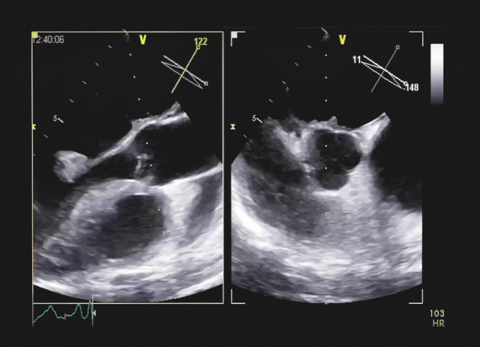

Wideo Pułapki Echokardiograficzne. Przypadek 39

dr n. med. Barbara LichodziejewskaPień płucny i jego zastawka. Tajemnicze obrazy.